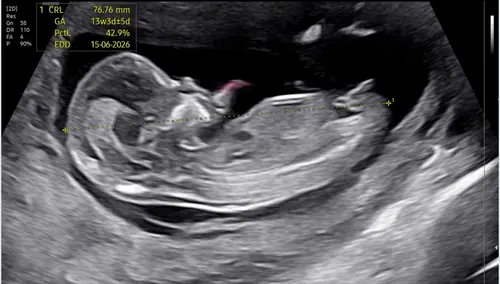

🩵🩷? 13+5

Wie wil een gokje wagen? Dit is baby 2. Volgende bericht deel ik baby 1 van de tweeling. Ben zoo benieuwd!